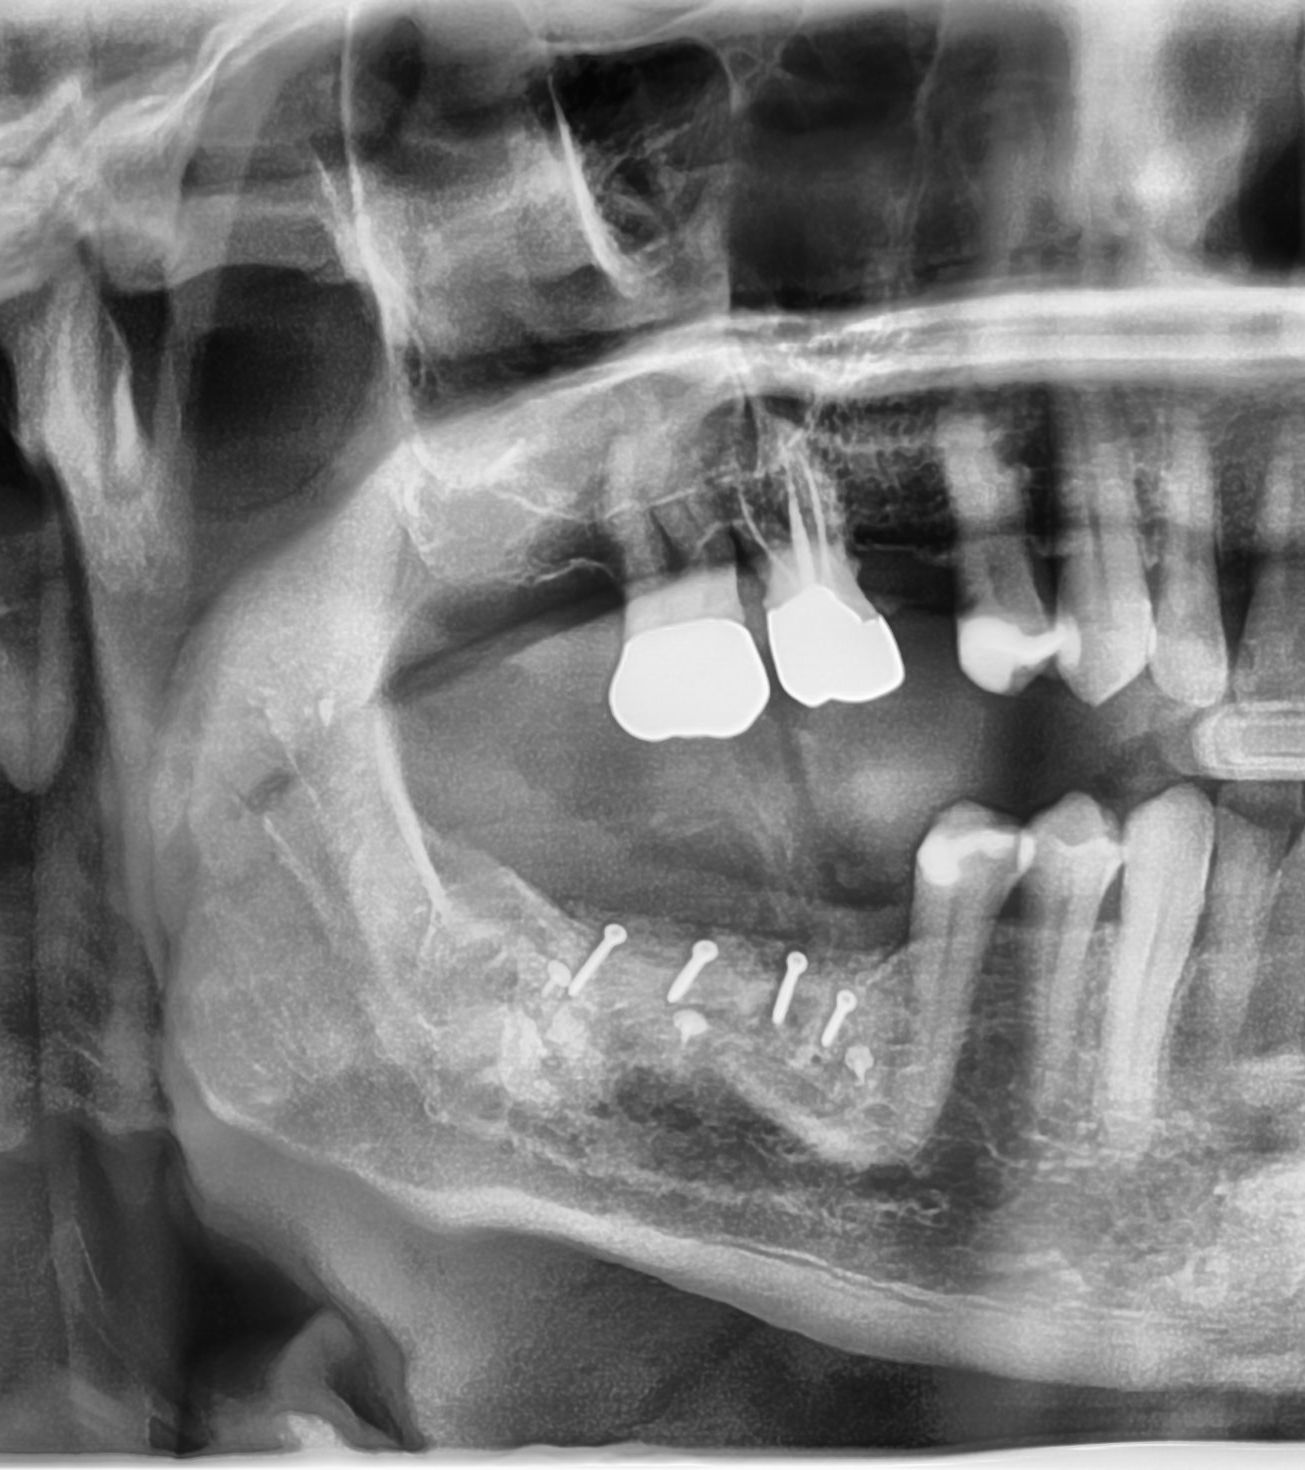

11/28 - X-ray scan after augmentationThree-dimensional augmentation with maxgraft® cortico - Dr. R. Würdinger

21/28 - X-ray scan of the augmented ridge after implantationThree-dimensional augmentation with maxgraft® cortico - Dr. R. Würdinger

24/28 - X-ray control scan after implant uncovering - excellent and stable osseous situationThree-dimensional augmentation with maxgraft® cortico - Dr. R. Würdinger

28/28 - Radiographic control of the final prosthesis - excellent stability of the augmented bone tissueThree-dimensional augmentation with maxgraft® cortico - Dr. R. Würdinger